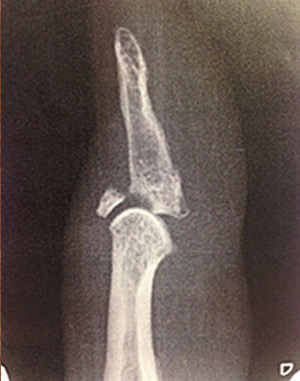

The diagnosis of mallet finger involves a physical examination and obtaining an X-ray of the injured finger. In some cases, other imaging techniques such as MRI scan may be recommended.

Patients who fail to achieve adequate relief are recommended for surgery which involves repairing the torn tendon. If the mallet finger involves a fracture of the bone fragment, then it can be stabilized and fixed using pins and a special K-wire.